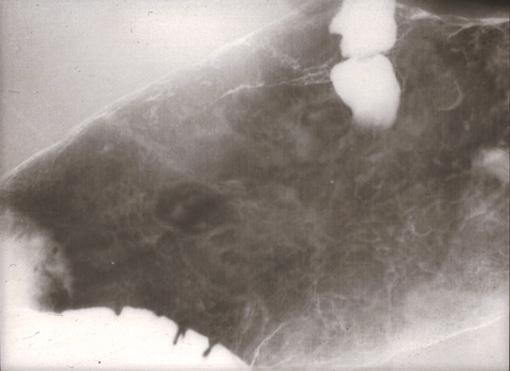

胃体部の広い範囲に認められたいわゆる早期胃悪性リンパ腫のX線像  半立位による背臥位の第2斜位での胃二重造影像です。噴門直下から胃体部の粘膜面を拡大してみた写真です。胃体中部から胃体上部の前壁、小弯、後壁、大弯と、ほぼ胃体部の全周にわたって、広い範囲に不整形の粘膜面がみられます。その内部には、数ミリから1.5cm大までの大小不同で顆粒状~結節状の粘膜遺残がみられます。比較的大きなものは、背の低い隆起を形成して、その形と辺縁は癌に比して、丸味を帯び、整です。

疾患(病理主体)の分類悪性リンパ系腫瘍/悪性リンパ腫

部位(臓器別)胃(部位)/2つ以上

検査方法X-P

病変の最大径(ミリ)10〜14

腫瘍の深達度sm